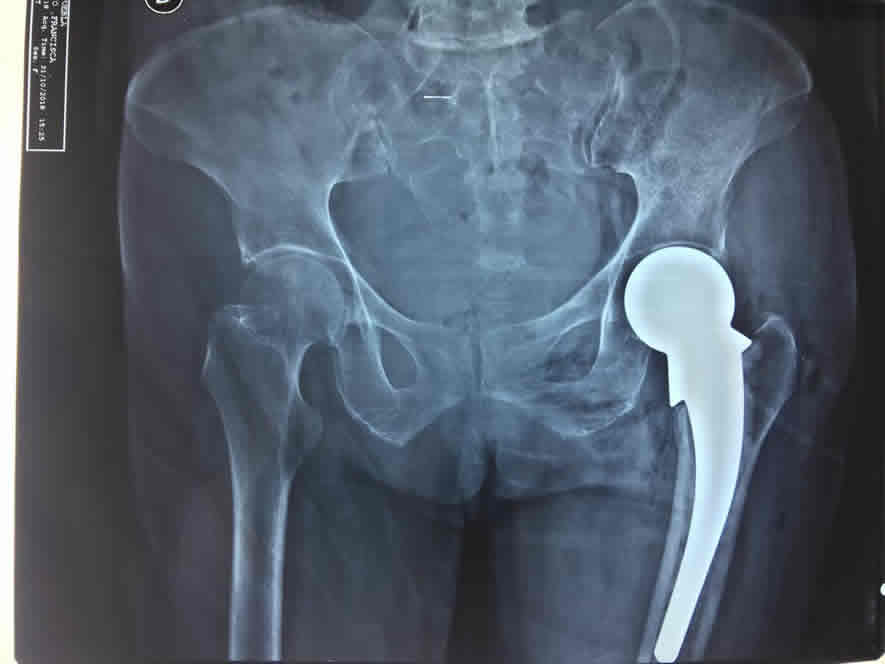

Dolor en cadera, rodilla, tobillo y hombro

Manejo de lesiones degenerativas o desgaste por la edad en cadera, rodilla, tobillo, hombro mediante la aplicación de infiltraciones intrarticulares, viscosuplementación y manejo en conjunto con terapia física y rehabilitación.

En caso de lesiones y limitación funcional avanzada se ofrece artroscopias o colocación de prótesis en cadera, rodilla y hombro.